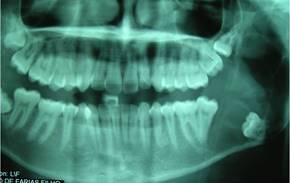

Paciente afrodescendiente, de sexo masculino, 17 años, estudiante, nacido en Fortaleza, estado de Ceará, en Brasil, que buscó atención en una clínica odontológica privada con quejas de supuración en la boca. Como nos informó la madre, durante aproximadamente un mes el paciente había sentido un mal sabor en la boca. Buscaron un cirujano dentista clínico que, al solicitar una radiografía panorámica de los maxilares, notó una lesión en la mandíbula y lo remitió al cuidado del cirujano bucomaxilofacial. En la anamnesis, no mencionó ninguna queja de dolor: solo mencionó mal sabor en la boca y mal aliento. En el examen físico extrabucal se observaron facies simétricas y ausencia de deformidades faciales. Cadenas ganglionares del complejo cervicofacial sin alteraciones. En el examen intrabucal era visible una supuración en la región del surco gingival lingual y distal 37. Elevación discreta en la región del trígono retromolar izquierdo con punto de fluctuación, de consistencia líquida. Examen de imagen (ortopantomografía) que muestra una extensa lesión osteolítica en la región del ángulo y rama ascendente mandibular izquierda, de aspecto expansivo, asociada al 38 incluido desplazado hacia el hueso basilar (Fig. 1).

Para una mejor evaluación de la extensión de la lesión, se solicitó una tomografía volumétrica de haz cónico de la región, donde se pudo observar sus límites y relaciones anatómicas circundantes (Fig. 2).